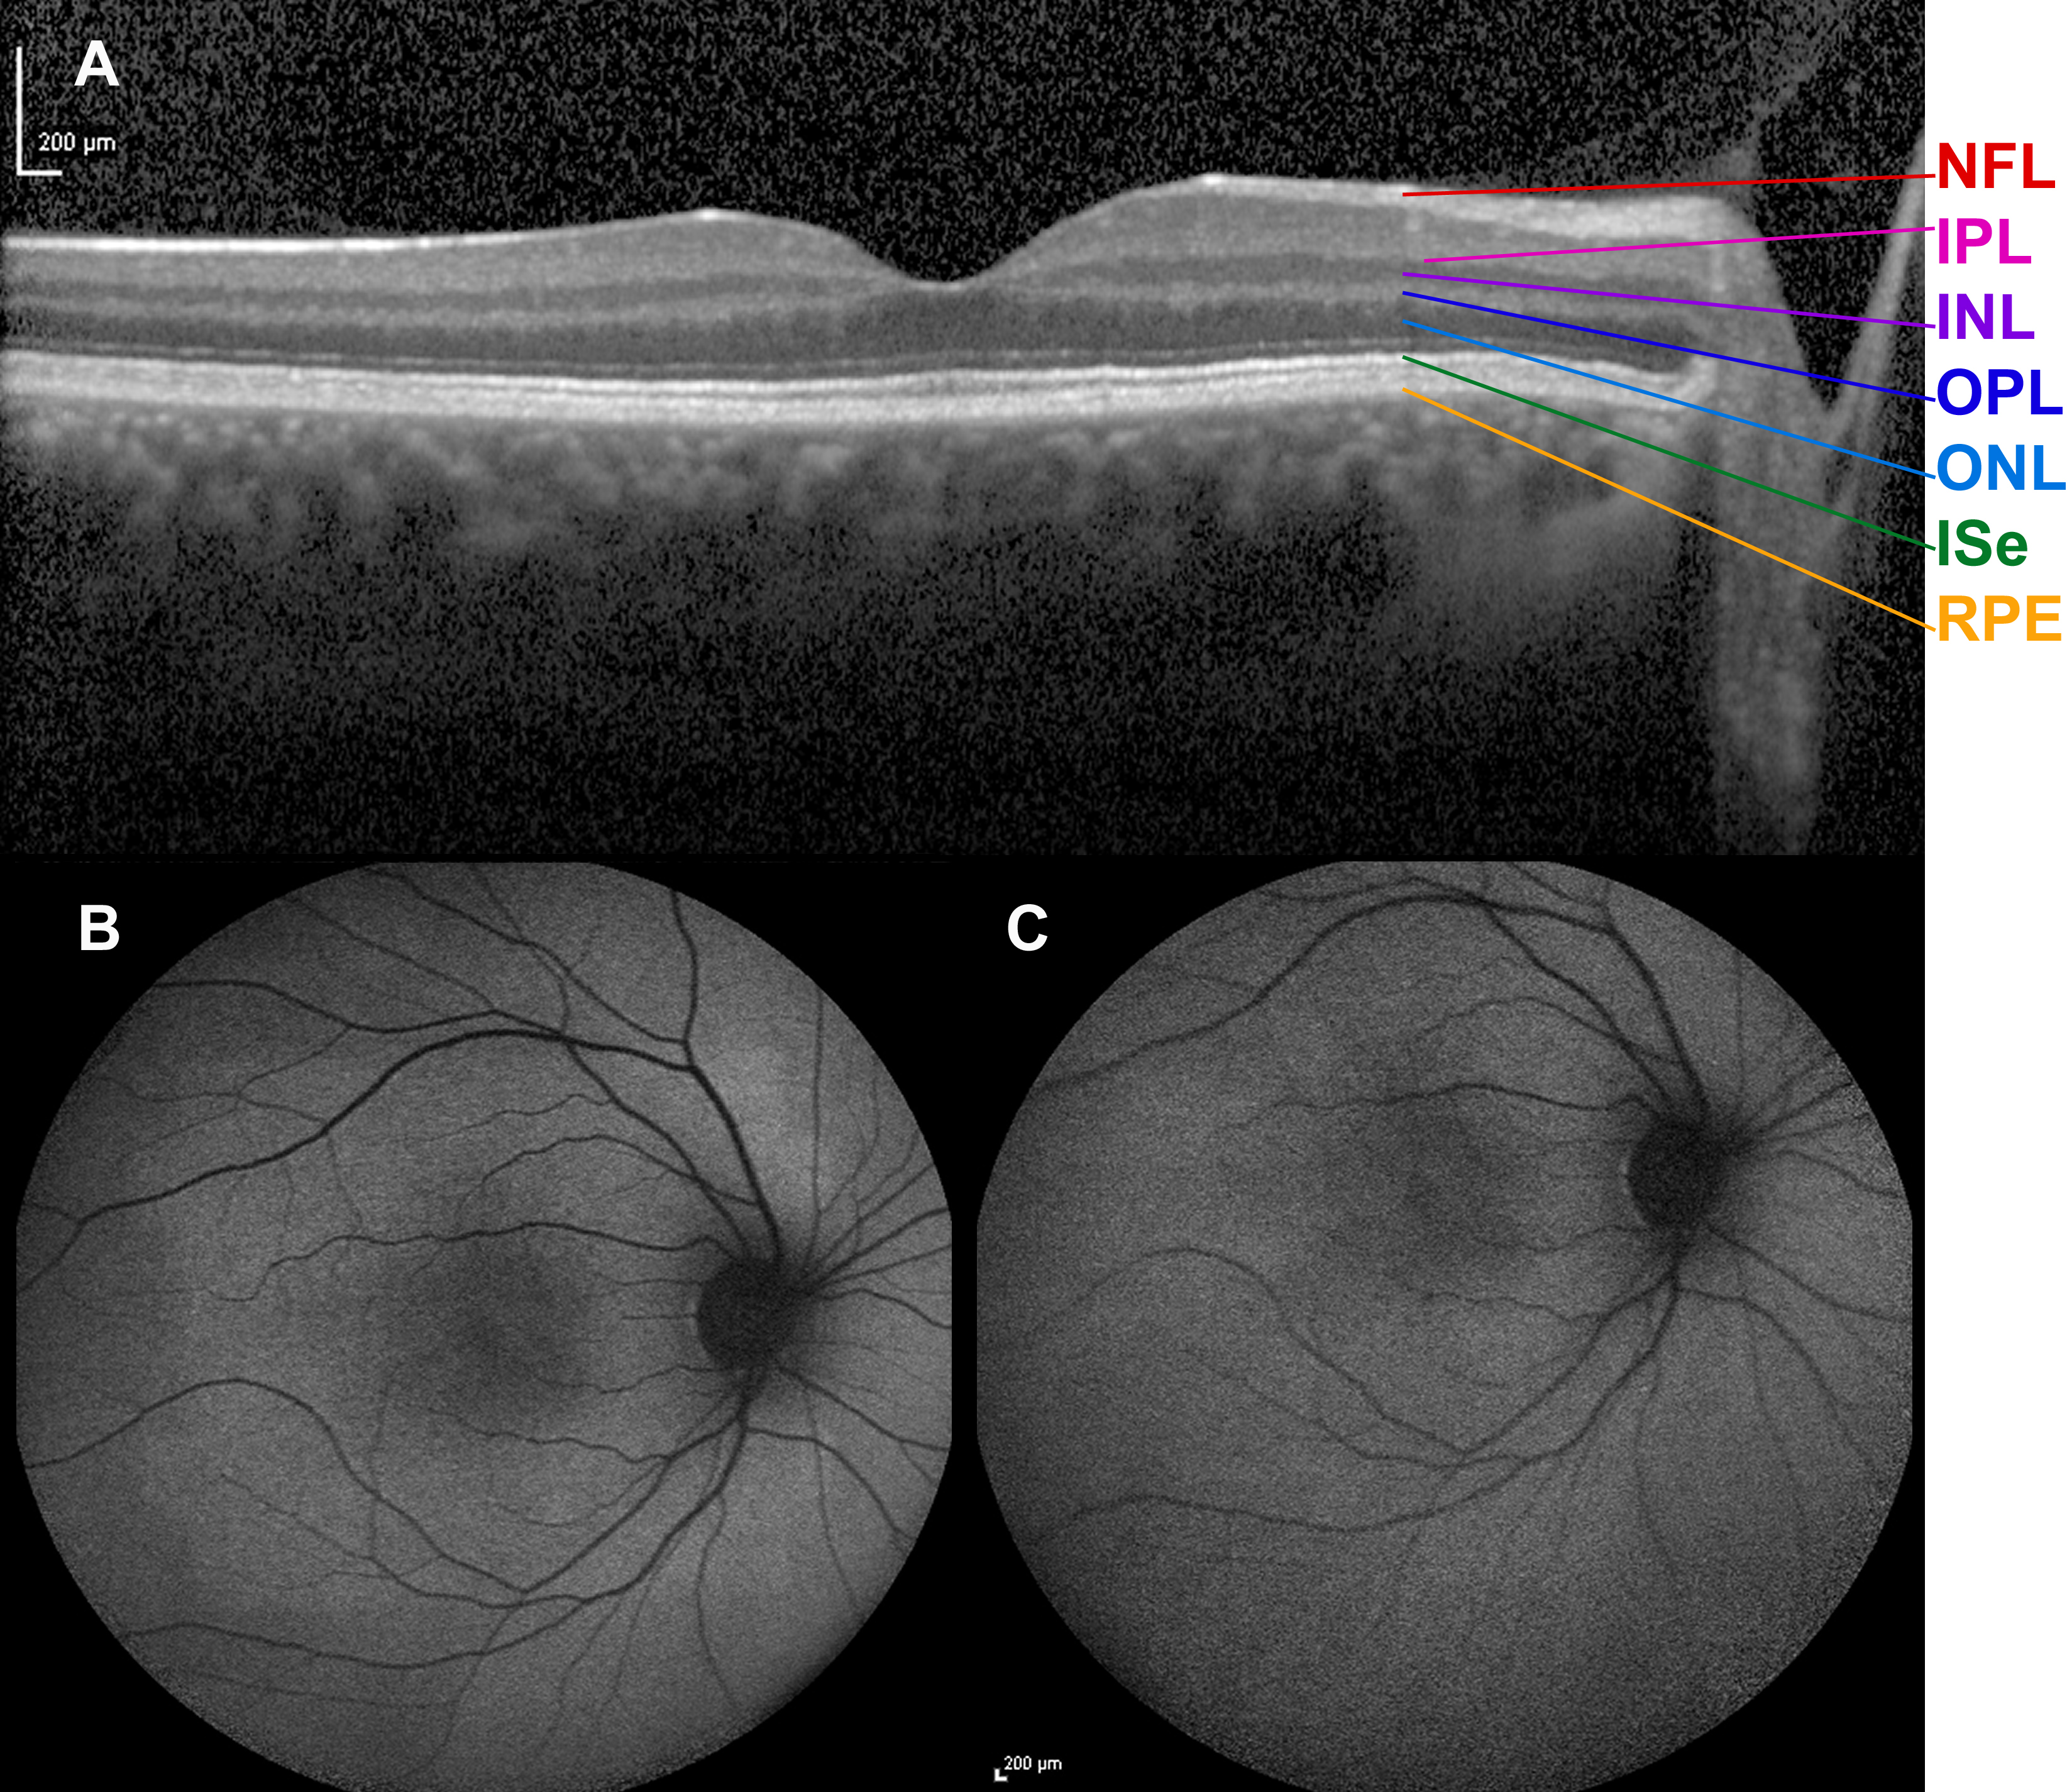

Figure 6. Spectral-domain optical coherence tomogram and fundus autofluorescence in a female carrier of RPGR ORF15 X-linked retinitis pigmentosa. Horizontal transfoveal spectral-domain optical coherence tomogram (A) from the left eye of the female carrier of XLRP after 2 h of dark adaptation at the age of 22 years. An ordered configuration

of the photoreceptor/retinal pigment epithelium complex is seen. Except a slightly undulating ellipsoid line, there seems

to be no obvious difference compared to the normal optical coherence tomogram of a healthy subject. Retina layers from bottom

upward: RPE=retinal pigment epithelium/Bruch’s membrane complex, ISe=inner segment ellipsoid, ONL=outer nuclear layer, OPL=outer

plexiform layer, INL=inner nuclear layer, IPL=inner plexiform layer, NFL=nerve fiber layer. Autofluorescence fundus photography

was performed at the age of 22 years. No abnormal pattern and thus no reminiscence of tapetal-like reflex was noted on imaging

obtained in the light adapted state (B, last image in a series of five images), or after 2 h of dark adaptation (C, first image in a series of five images). The patient’s autofluorescence fundus images displayed a sensitivity to dark adaptation

that is also known from subjects with normal eyes. Thus, a progression was seen from the first to the last image in that the

intensity of autofluorescence gradually increased, except in the fovea. This phenomenon is believed to reflect the bleaching

of the photoreceptor photopigment as the result of continued exposure to blue light and the shielding of the foveal fluorophores

by the xanthophyll pigment. The autofluorescence images showed no trace of the tapetal reflex pattern, neither before nor

after bleaching.